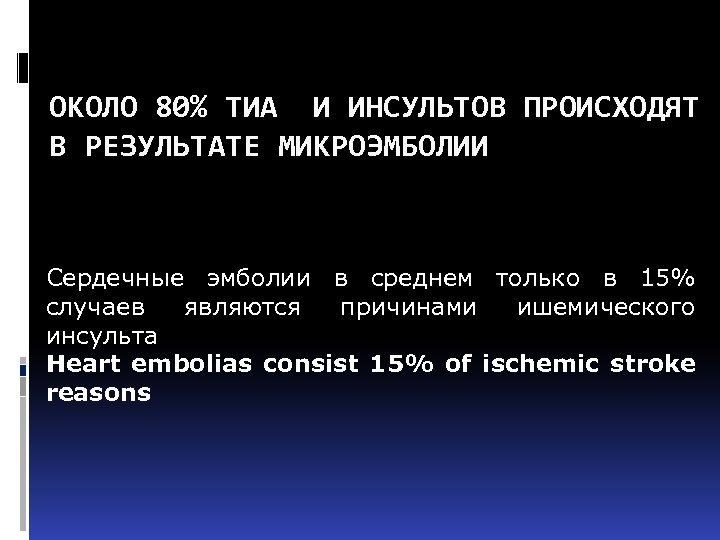

ОКОЛО 80% ТИА И ИНСУЛЬТОВ ПРОИСХОДЯТ В РЕЗУЛЬТАТЕ МИКРОЭМБОЛИИ Сердечные эмболии в среднем только в 15% случаев являются причинами ишемического инсульта Heart embolias consist 15% of ischemic stroke reasons

ОКОЛО 80% ТИА И ИНСУЛЬТОВ ПРОИСХОДЯТ В РЕЗУЛЬТАТЕ МИКРОЭМБОЛИИ Сердечные эмболии в среднем только в 15% случаев являются причинами ишемического инсульта Heart embolias consist 15% of ischemic stroke reasons